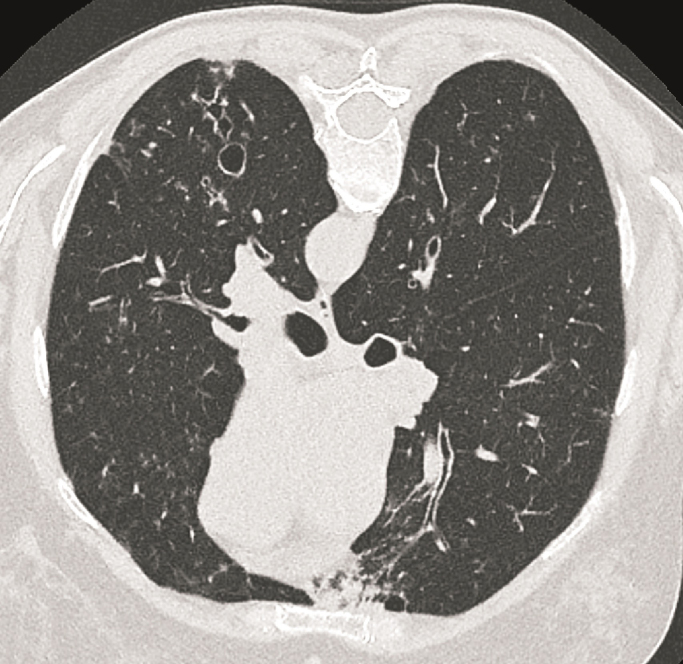

Case presentation: Hereby we describe a 53-year-old patient with severe uncontrolled asthma who presented with chronic hypercapnic respiratory failure. During her medical workup, she was noted to have several comorbidities leading to her respiratory failure. The patient had radiological evidence of bronchiectasis with recurrent episodes of infection, and a severe deformity of the spine due to Kyphoscoliosis. Probably the kyphotic component of this deformity had worsened due to a long history of oral steroid use leading to severe osteoporosis and consequent vertebral compression fractures reaching a Cobb angle of 73 degrees. This was probably caused by the patient's non-compliance with inhaler therapy and an excessive reliance on oral steroid use. Her respiratory failure was treated with domiciliary noninvasive positive pressure ventilation and 24-hour oxygen therapy and her symptoms improved.